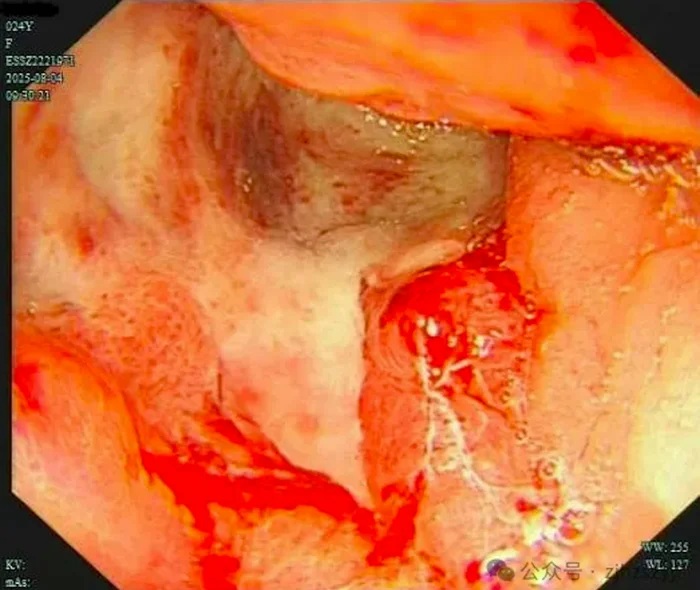

Kết quả nội soi khiến ai nấy không khỏi choáng váng: một vết loét lớn đã chiếm trọn hang vị dạ dày, lớp niêm mạc trở nên cứng và mất đàn hồi, nhìn giống như “miếng da thuộc”. Sinh thiết sau đó xác nhận Tiểu Văn mắc ung thư biểu mô tế bào nhẫn dạ dày, căn bệnh chiếm khoảng 10% tổng số ca ung thư dạ dày và được coi là một trong những thể ác tính nhất.